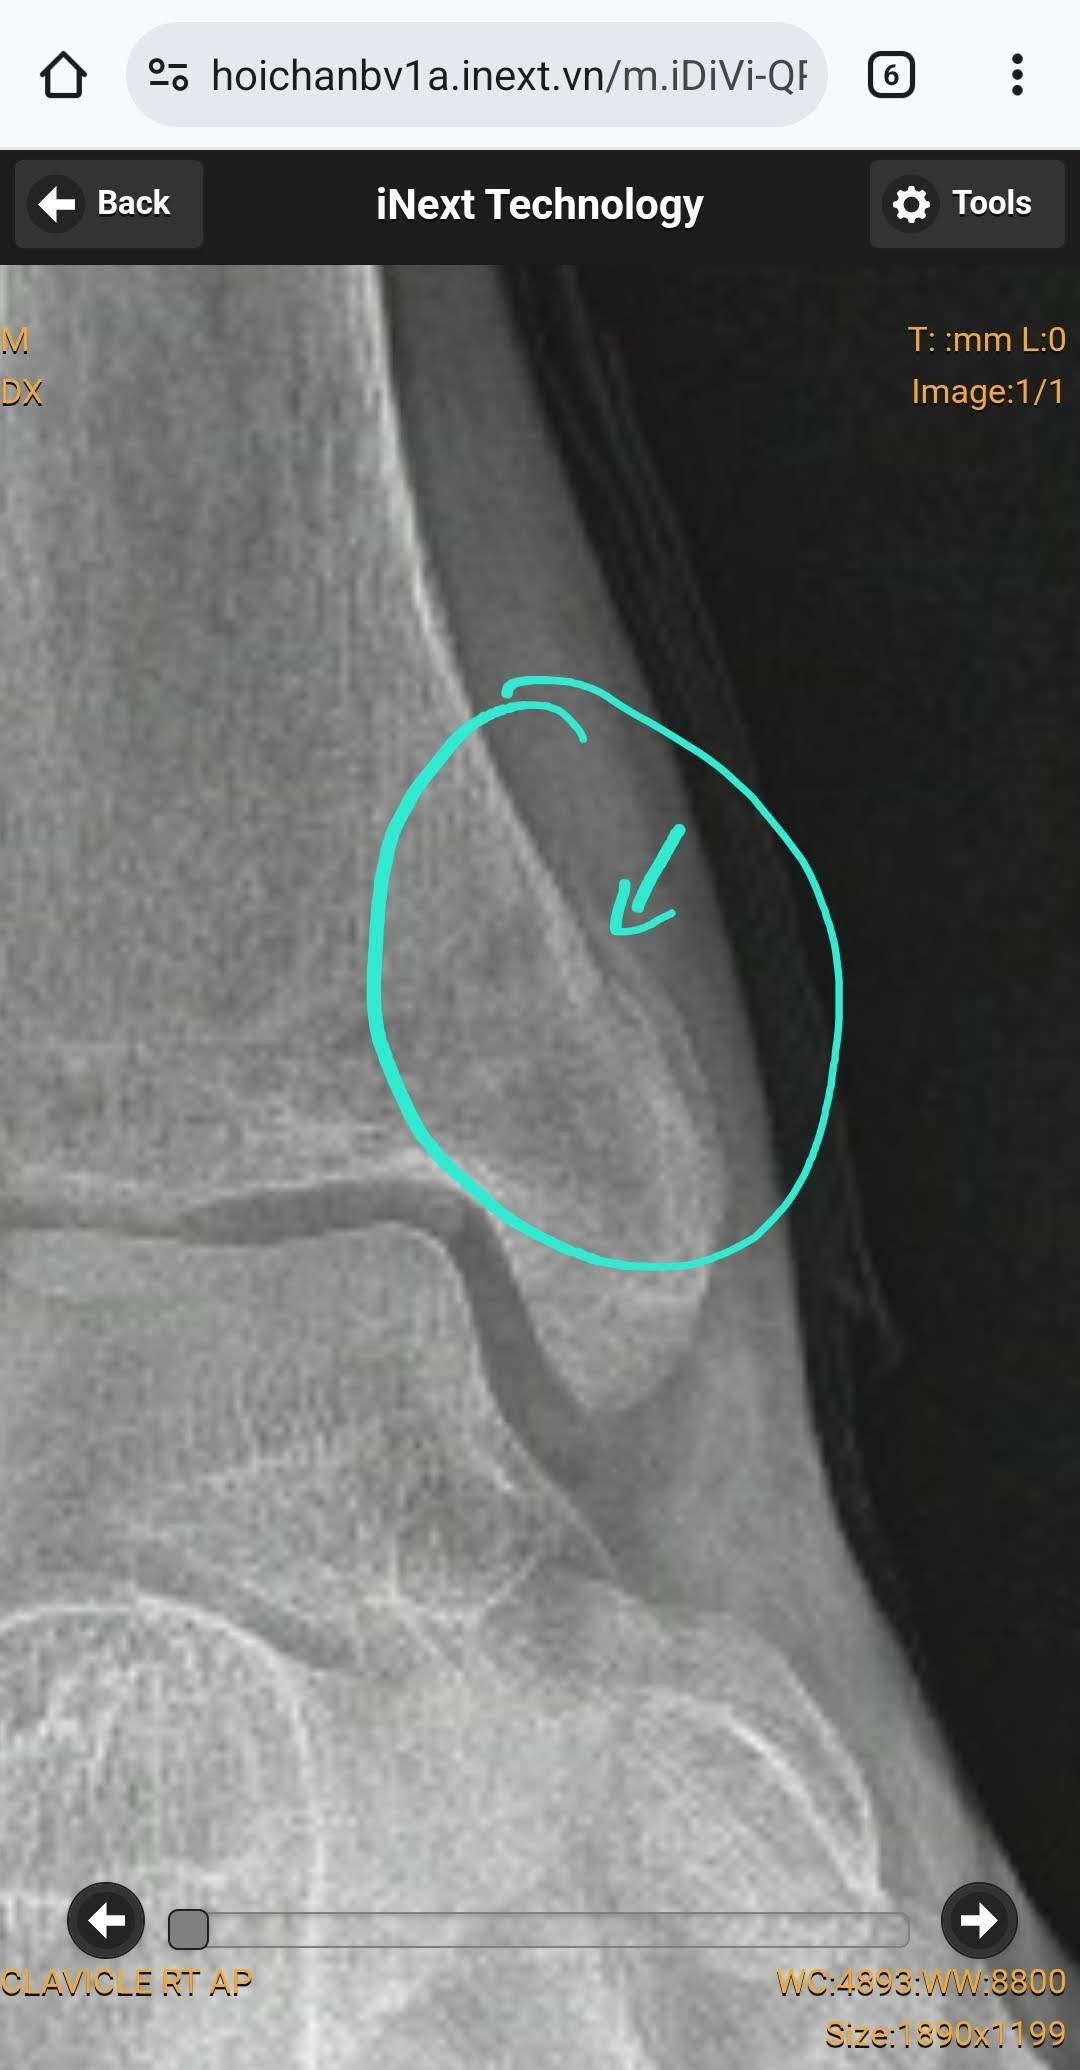

Bệnh nhân nữ 22 tuổi. Đau ngực khi thở trong vài ngày nay và khó thở. Đến phòng cấp cứu do các triệu chứng này, với CRP tăng nhẹ 44, D-dimer 5.2 µg/mL (bình thường <0.5 µg/mL), TnT bình thường, CTM bình thường. Không ghi nhận triệu chứng khác. Thỉnh thoảng hút thuốc, uống bia chủ yếu với bạn bè vào cuối tuần, không quá nhiều. Không có tiền sử bệnh mãn tính. Đang dùng thuốc tránh thai. HA 110/80, M 100.